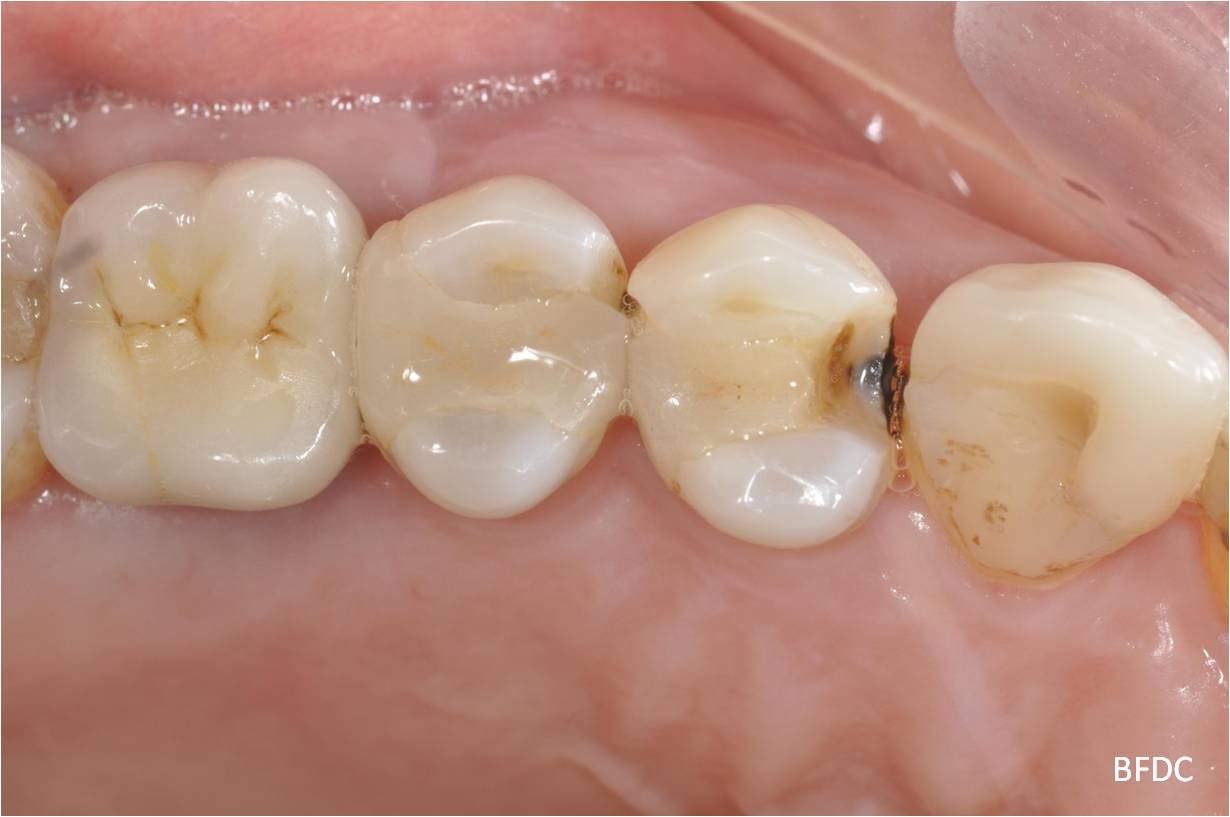

10年前原陶瓷崁體損壞